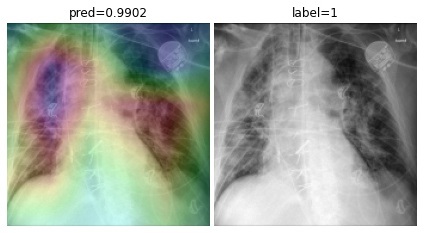

Accuracy score is 81.04%, with f-scores of 0.85 and 0.76 for CP and CAP classes, respectively. In a number of cases, especially in the first stages of virus progression, CP has unilateral findings. Also, CAP may cause bilateral consolidations. Therefore, some cases are expected to be misclassified between CP and CAP. From the confusion matrix, it could be seen that a relatively high number of images are misclassified between CAP and normal. A potential reason for this issue is considered to be related to wrong labeling. Besides, some CAP CXRs are from patients with early-stage disease development. To confirm the model performance, Grad-CAMs are plotted in Fig. 19.

Refer to caption

Figure 19: COVID-CXNet multiclass classification visualization results

The model is properly looking at one lobe for detecting CAP and both lobes for CAP and normal images. There are some wrong labels, nevertheless. A figure containing more visualizations is found in Appendix C. To further enhance statistical scores, a hierarchical approach is implemented. In the first level, we classify images into normal and pneumonia classes. In the second level, pneumonia images are categorized into CP and CAP. Final confusion matrix is illustrated in Table 5.